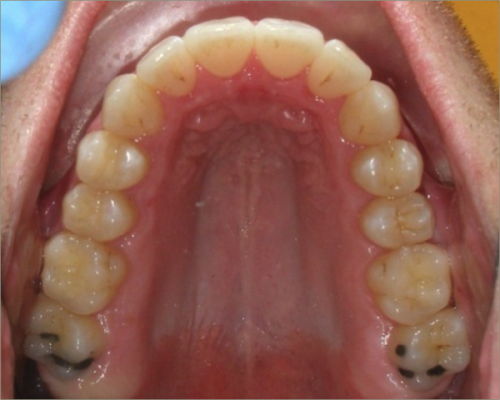

30 year old male:

Diagnosis:

- Upper and lower crowding

- Narrow upper & lowerarch forms

- Open bite

Treatment:

- Invisalign

- Non-Extraction

- 27 months